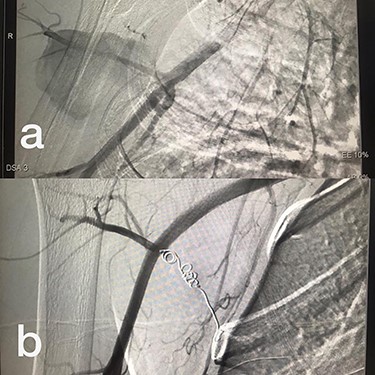

Sites of injury included 6 Posterior Tibialis arteries (27.2%) (Fig. 1), 2 deep femoral arteries (9.09%), 2 Superficial femoral arteries (9.09%) and 2 maxillary arteries (9.09%). We had only one injured artery (4.54%) in each of the following sites: internal pudendal a., Axillary a. (Fig. 2), Proneal a., Lumbar a., External carotid a., Anterior Tibialis a., common iliac a. (Fig. 3), temporal a., Thoracic aorta and Internal iliac artery (Fig. 4).

(a) Posterior Tibialis artery before intervention, (b) after endovascular stent graft deployment.